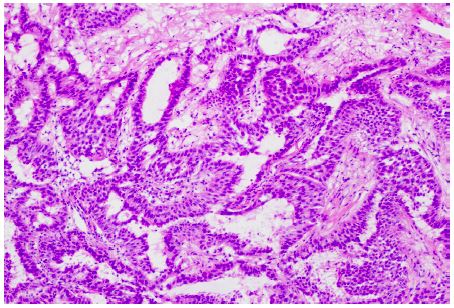

A 60-year-old female presented to the ED for dyspnea and tachycardia. A CT angiogram of the chest incidentally revealed a left upper lobe spiculated pulmonary lesion (1.4 cm) that was suspicious for malignancy; no mediastinal hilar lymphadenopathy was noted. CT/PET demonstrated a single hypermetabolic left upper lobe lesion with no other evidence of disease. A robotic wedge resection and left upper lobectomy was completed; pathology revealed an invasive pulmonary adenocarcinoma that invaded the visceral pleura, as confirmed on elastin stain, with negative margins; 1/12 nodes were positive for metastatic carcinoma (T2aN1; Figure 1).

Figure 1: Lung adenocarcinoma histology. The nested pattern with nuclear hyperchromasia (100x), consistent with adenocarcinoma.